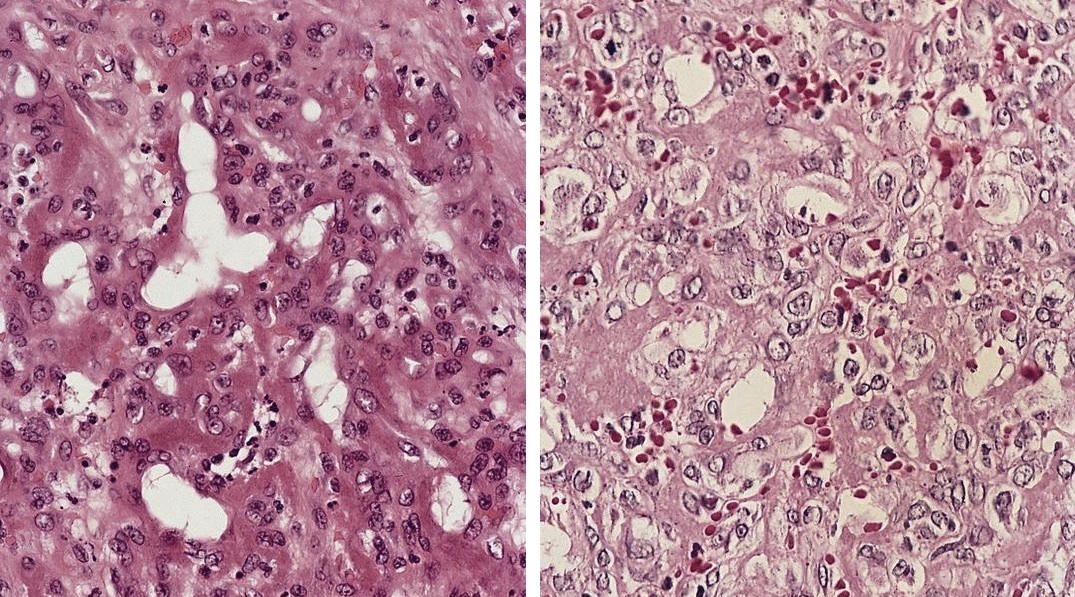

Microscopic (histologic) description

- Nodal architecture obscured by ill defined lipogranulomas

- Involvement of sinuses by macrophages with foamy cytoplasm

Microscopic (histologic) images

Contributed by Mark R. Wick, M.D.